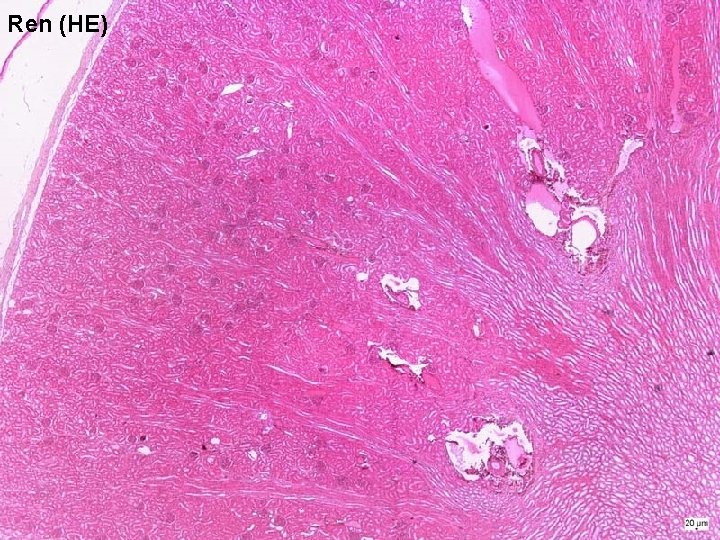

Ren (HE)

Ledvina (ren, nephros) Kůra: - „čistá“ kůra - žíhaná kůra - sloupce korové Dřeň: - pyramidy (10 – 18) - papily s otvory vazivové pouzdro tukové pouzdro

striae medullares cortex medulla